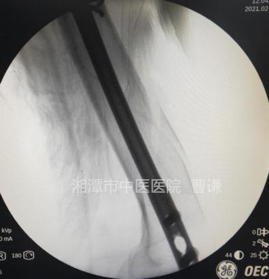

这是一例胫骨中下段螺旋形骨折,同样通过微创置入钢丝捆扎复位,置入钢板

术中切口外观照片。